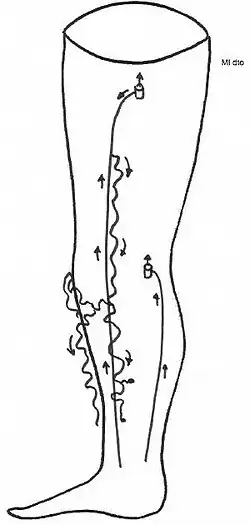

| Perna afetada por varizes | |

Varizes são dilatações ou tortuosidades das veias superficiais do corpo.[2][1] Geralmente formam-se nas pernas imediatamente por baixo da pele.[3] Na maior parte dos casos não se manifestam outros sintomas, embora algumas pessoas possam sentir sensação de plenitude, fadiga, pressão ou dor no local.[2] Entre as possíveis complicações estão a ocorrência de hemorragias ou tromboflebite.[2][1] Quando as varizes se formam no escroto a condição é denominada varicocelo e as do ânus são denominadas hemorroidas.[1]

Além do problema estético, habitualmente o paciente queixa-se de dores nos membros inferiores, sobretudo quando está de pé. Estas dores são muitas vezes referidas como uma sensação de peso ou tensão mas pode também ser referido prurido e ardor. Estes sintomas são devidos a um aumento da pressão venosa distal. Poderá haver edema do membro afectado, sobretudo quando o paciente é obrigado a permanecer longas horas de pé, parado.

Com a evolução e o agravamento da doença desenvolve-se nos pontos de maior declive um processo de distrofia tissular caracterizado por uma reacção inflamatória com endurecimento cutâneo e do tecido celular sub-cutâneo (lesão pré-ulcerosa); se a doença venosa não for tratada, o processo ulceroso desenvolve-se e pode arrastar-se durante anos .

Esta dilatação venosa, a que chamamos varizes, é portanto uma manifestação da doença venosa e não a doença propriamente dita e vai originar um fluxo sanguíneo retrógrado de cima para baixo com aumento da pressão venosa distal e as suas consequências nefastas a nível da perna e do pé.